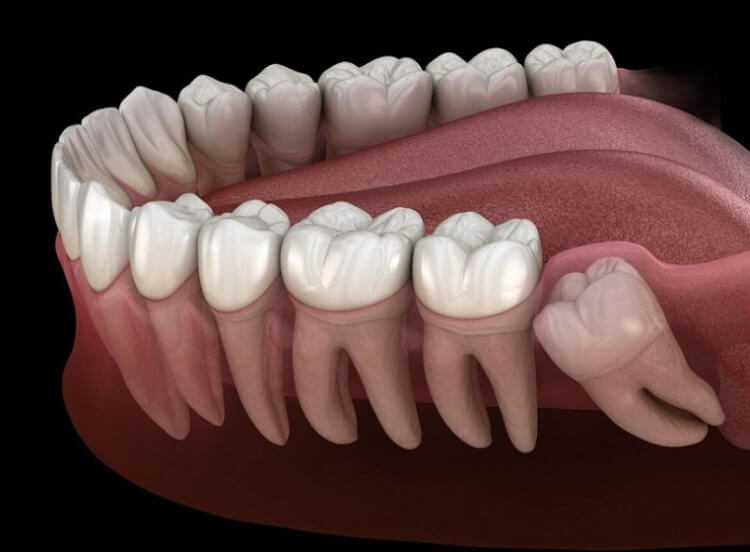

В период между 16 и 20 годами у многих людей начинают прорезаться зубы мудрости, также именуемые как третьи моляры. Так как они вырастают последними, во рту часто не остается для них места, поэтому в конечном итоге третьи моляры вырастают под наклоном и доставляют болезненные ощущения. В результате их приходится удалять хирургическим путем, что заставляет людей серьезно понервничать. К счастью, в итоге операция обычно проходит без серьезных последствий. Но эта проблема для представителей некоторых народов не актуальна — например, у жителей Мексики коренные зубы никогда не прорезаются. Это связано с генетическими изменениями, которые произошли около 400 лет назад и разделили людей на «мудрозубых» и «немудрозубых». Давайте разберемся, почему именно возникли эти изменения и для чего вообще нужны зубы мудрости?

Когда-то давно дополнительные зубы на задней части челюсти были необходимы для пережевывания твердой пищи. В частности, речь идет о сыром мясе и растениях, которые до изобретения огня были очень жесткими для отрывания и пережевывания. Как только наши предки научились готовить еду на костре, зубы мудрости быстро превратились в рудименты — органы, которые утратили свои полезные функции. Сегодня большинству людей они удаляются из-за неправильного роста. Но иногда они прорезаются ровно и их оставляют, а в будущем используют в качестве опорных зубов при установке мостовидных протезов.

Как правило, зубы мудрости растут именно таким неудобным образом